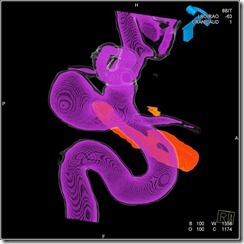

Case 1: Immediate post coiling 3D angiogram to look for residue

Post coiling 3D angiogram with dual volume recon on an Acom aneurysm showing the coil mass in silver and the contrast filled arteries in golden brown. The aneurysm is well coiled with no residue. However the base of the coil mass is irregular indicating freshly done procedure. With time, base is likely to be covered up with endothelium and the arterial outline would become smooth.